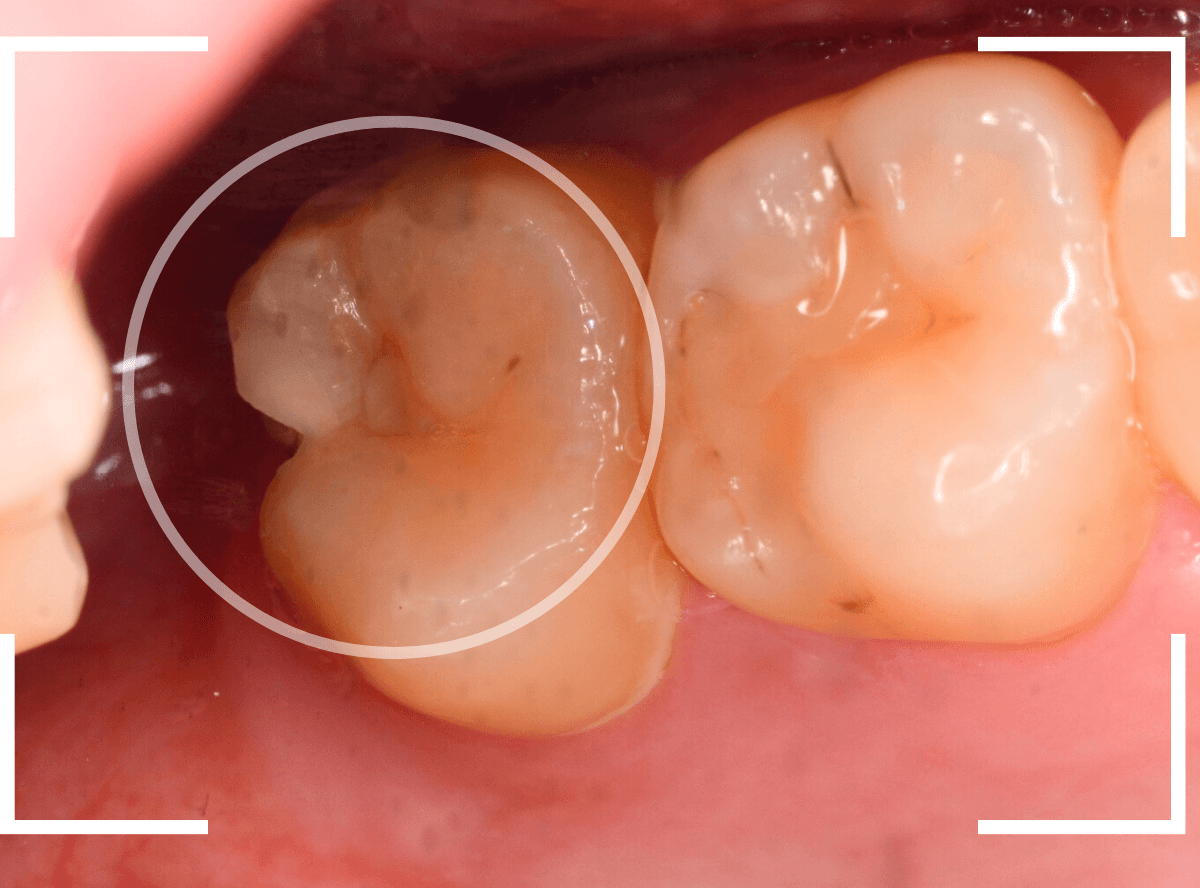

Case.1 症状があったのに、半年間虫歯を放置した!

半年くらい前から、上の奥歯に違和感を感じるという患者さんが来院されました。

しみるとか痛いというほどの症状ではないそうです。

う~ん、パッと見は問題なさそうに見えます。

レントゲン写真で確認します。

一番奥の歯に明らかに大きな虫歯がありました。

奥歯の歯ブラシが届きづらい部分から虫歯になってしまったと思われます。

私が初見目視で確認した時もわからなかったですからね。

青い部分が痛みを感じる神経、赤い部分が虫歯です。

ここまで虫歯が神経まで近いと、通常であれば、大きな痛みやしみの症状があってもおかしくない状況です。

症状がないうちに治療を進めた方が良いです。